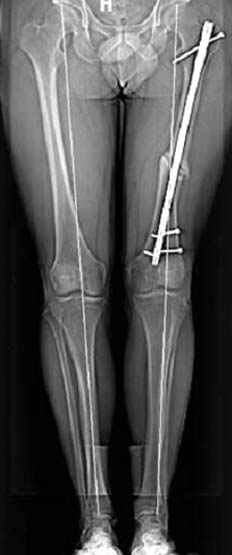

пластическая модель; и коррекция бедра аппаратом Илизарова.